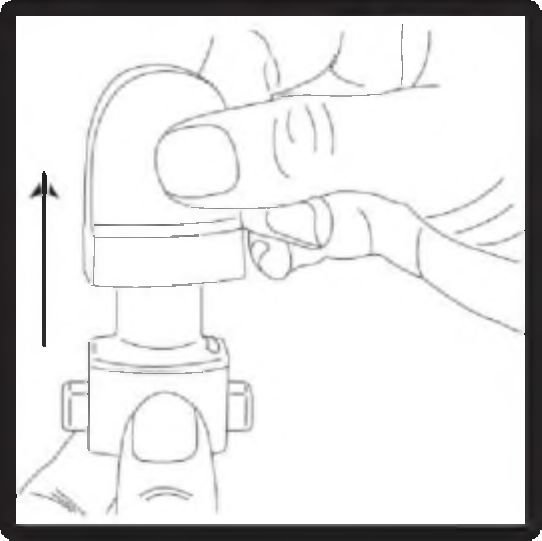

1. Kapağı çekerek çıkarın.

2. Cihazın alt kısmını sıkıca tutarken ağız parçasını ok yönünde çevirerek açın.